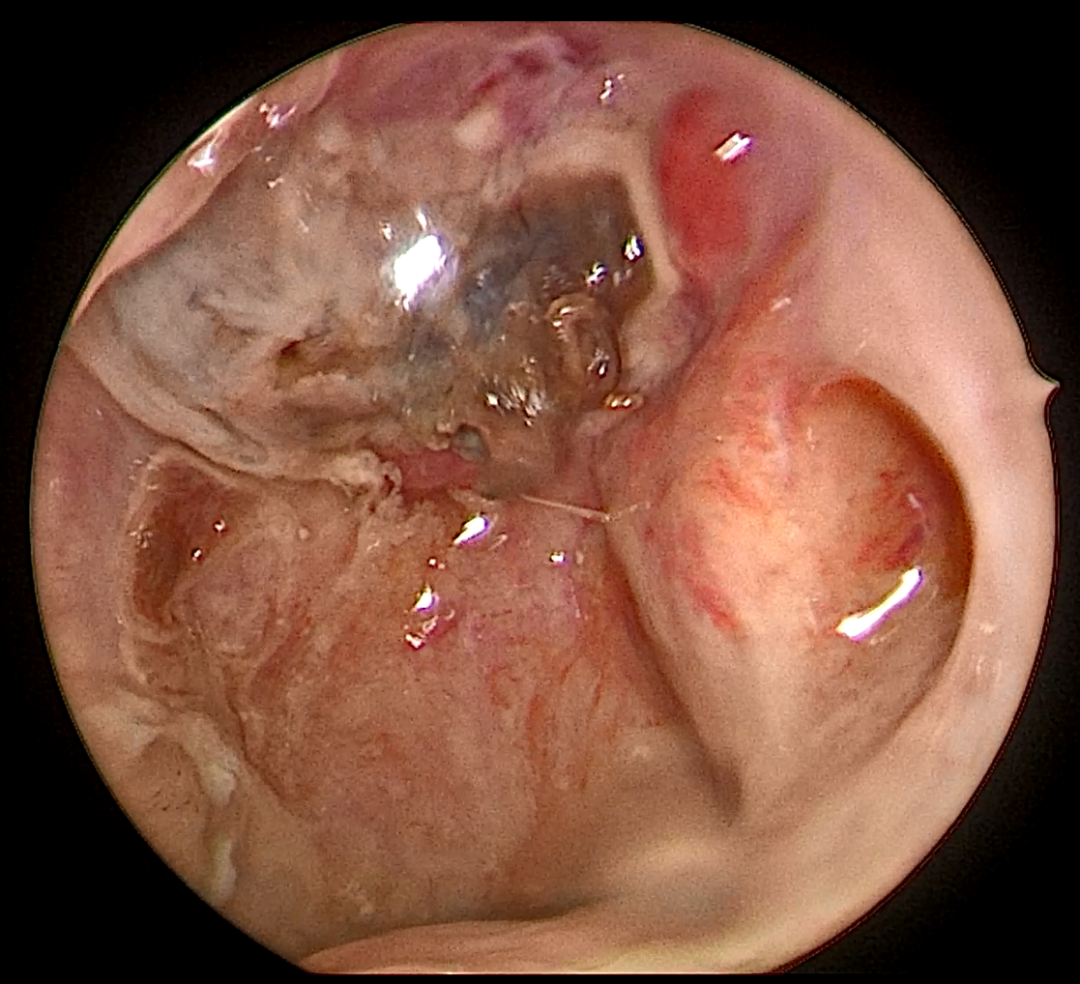

内镜检查:双侧咽隐窝区域坏死及肉芽样组织,表面覆盖脓性分泌物